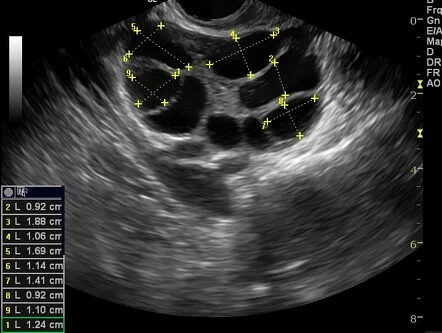

- Ovarian Reserve Testing: An antral follicle count (AFC) is performed early in the cycle to measure the number of resting follicles and predict response to stimulation.

- Follicular Monitoring: Tracks the growth of egg-containing follicles and measures endometrial thickness (uterine lining) to determine the best time for ovulation, IUI, or egg retrieval.